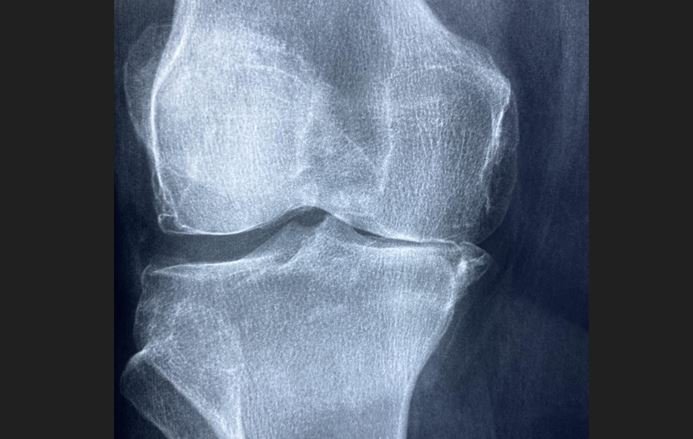

Hrskavica je glatko, amortizujuće tkivo koje omogućava zglobovima nesmetano kretanje. Kada se ošteti, rijetko se prirodno obnavlja, ostavljajući pacijente sa ukočenošću, oticanjem i dugotrajnim bolom.

Kada se injektuje u zglob, gel djeluje kao struktura koja podstiče vlastite ćelije tijela na regeneraciju zdrave hrskavice. S vremenom, zglob ponovo dobija prirodnu amortizaciju i pokretljivost, funkcionišući kao da nikada nije bio oštećen. Za razliku od umjetnih implantata koji se mogu trošiti ili zahtijevati zamjenu, ovaj pristup fokusira se na pravu regeneraciju tkiva.

Rani rezultati su obećavajući: pacijenti pokazuju poboljšano kretanje, smanjen bol i dugoročno iscjeljenje koje do sada nije bilo moguće. Ako veći klinički testovi potvrde ove nalaze, gel bi mogao postati novi standard u liječenju oštećenja zglobova, zamjenjujući operacije.